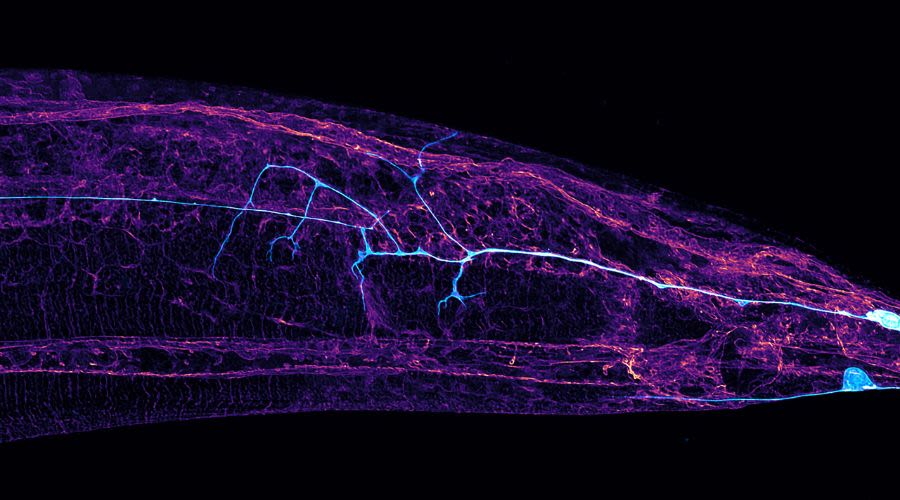

Viruses such as SARS-CoV-2 can cause fusing of brain cells

We discovered that viruses such as SARS-CoV-2 can cause our nerve cells to fuse, severely compromising their function. Our research also revealed that this is caused by viral fusogens (specialised surface molecules) becoming present on the nerve cells and inducing them to fuse — a mechanism never understood before.